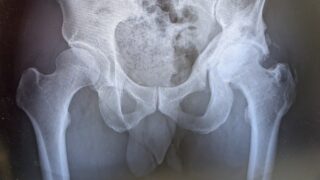

股関節痛治療 術後3ヶ月検診 8月にやった異所性骨化巣の切除手術から3ヶ月。再発防止のダイドネル錠の服用が終了したタイミングということらしいです。現在の状況上から両方の傷口が写るように撮影したもの8月の手術跡。痒みが、、、2年前の手術跡現在の状況はっきりいって芳しくない... 2025.11.20 股関節痛治療